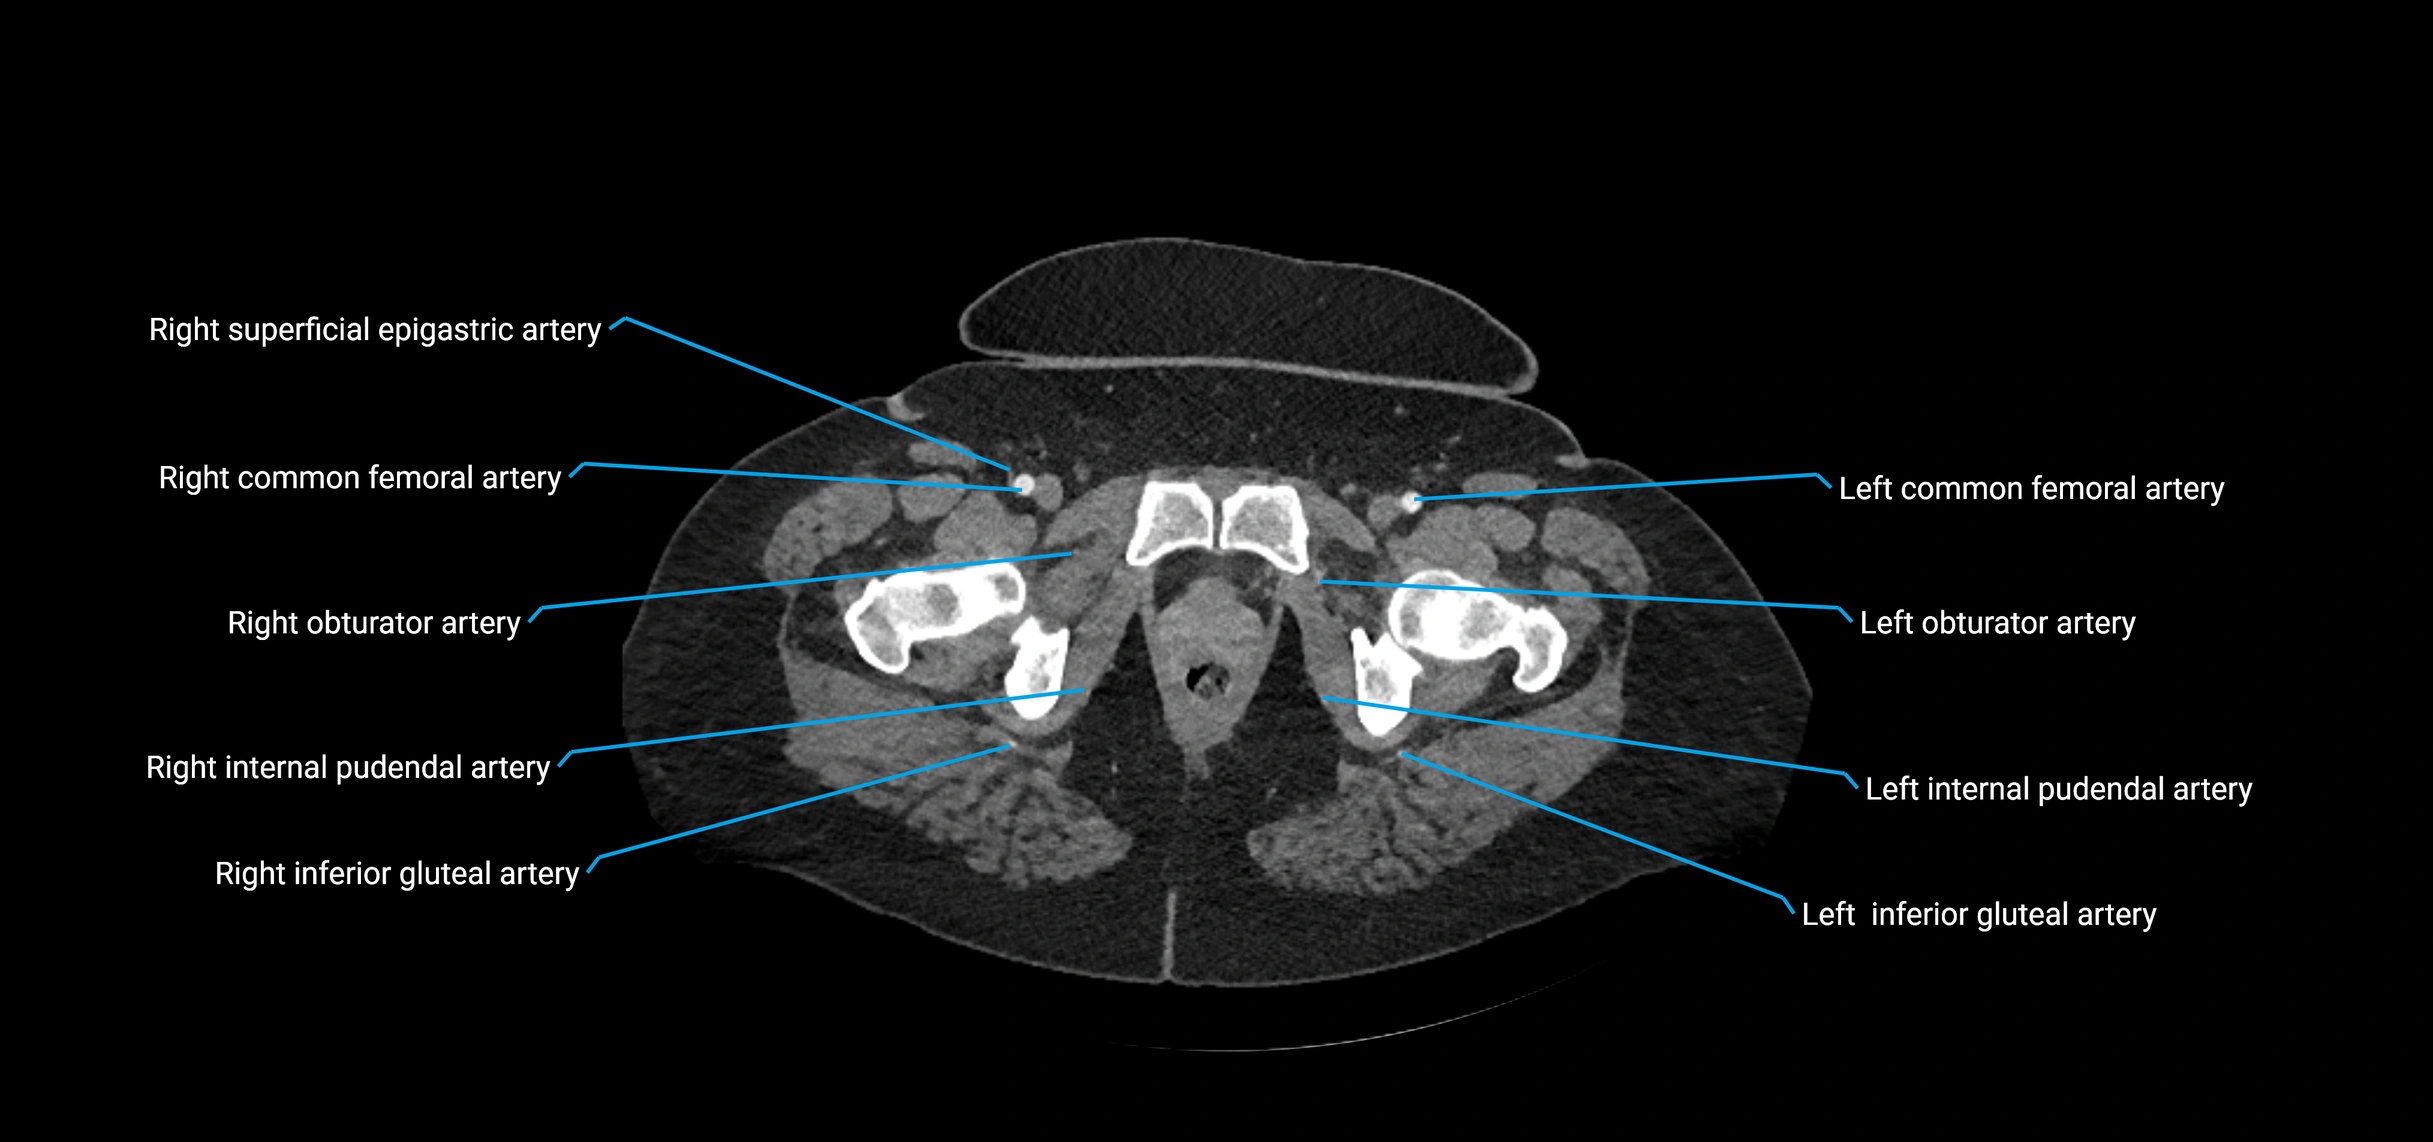

Contrast-enhanced CT (CTA):

• Gold standard for abdominal aortic imaging

• Provides excellent detail of lumen, wall, aneurysm, thrombus, and branch vessels

• Multiplanar and 3D reconstructions help in aneurysm measurement, stent graft planning, and dissection evaluation

• Detects acute rupture, traumatic injury, or occlusion with high sensitivity